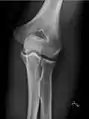

- زانو - AP و جانبی. پروجکشنهای داخلی کندیلار(Condular) در صورت درخواست.

- استخوان کشکک - تصویر افقی مرئی

زانوی راست، قدامی خلفی

زانوی راست، جانبی

استخوان کشکک (کمی انحراف) افق مرئی